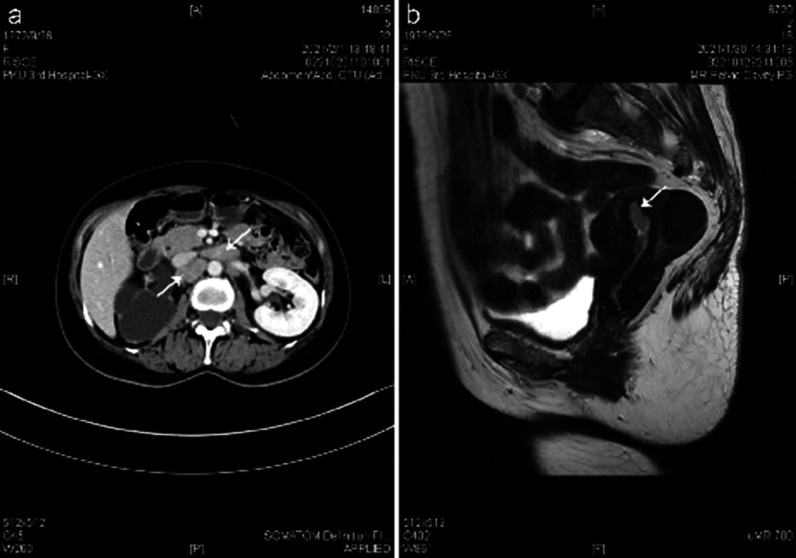

The results of preoperative laboratory tests are presented below (Table 1). Both CT and MRI revealed thickened endometrium and multiple enlarged lymph nodes in the pelvis, which suggested great possibilities of endometrial cancer with lymph node metastasis (Fig. 1). Abdominal ultrasound showed severe right hydronephrosis and right ureter dilatation. CT urography (CTU) enhancement demonstrated right urinary tract dilatation, right hydronephrosis and hydroureter, right kidney atrophy and stenosis of the right lower ureteral lumen. Her right kidney function was severely impaired, but the left kidney compensated enough so her renal function was normal seen under the renal dynamic imaging. PET/CT revealed increased fluorodeoxyglucose (FDG) uptake in the uterine cavity and there were multiple lymph nodes present in the retroperitoneal and bilateral iliac vascular areas (Fig. 2). After consultation, radiologists and gynecological oncologists all suspected the enlargement of lymph nodes were due to tumor cell infiltration based on the diagnosis of endometrial carcinoma.

Fig. 1.

Imaging findings of CTU and MRI. a The arrows pointed to the enlarged lymph nodes. b The arrow pointed to thickened endometrium